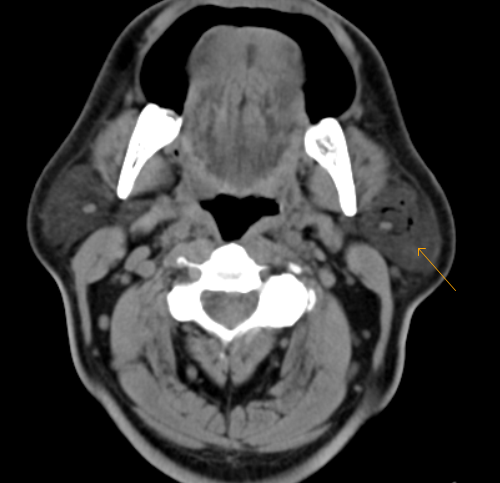

Pneumoparotid-CT

Pneumoparotid refers to air within the parotid gland without any demonstrable inflammation or infection. This is caused by reflux of intra-oral air into the parotid gland through Stenson’s duct. It is associated with any process that significantly increases intra-oral pressure. Intra-oral pressure must increase enough to overcome the small, slit like orifice of Stensen’s duct with surrounding redundant mucosal folds that normally prevent reflux of salvia and air into the duct and the parotid gland.